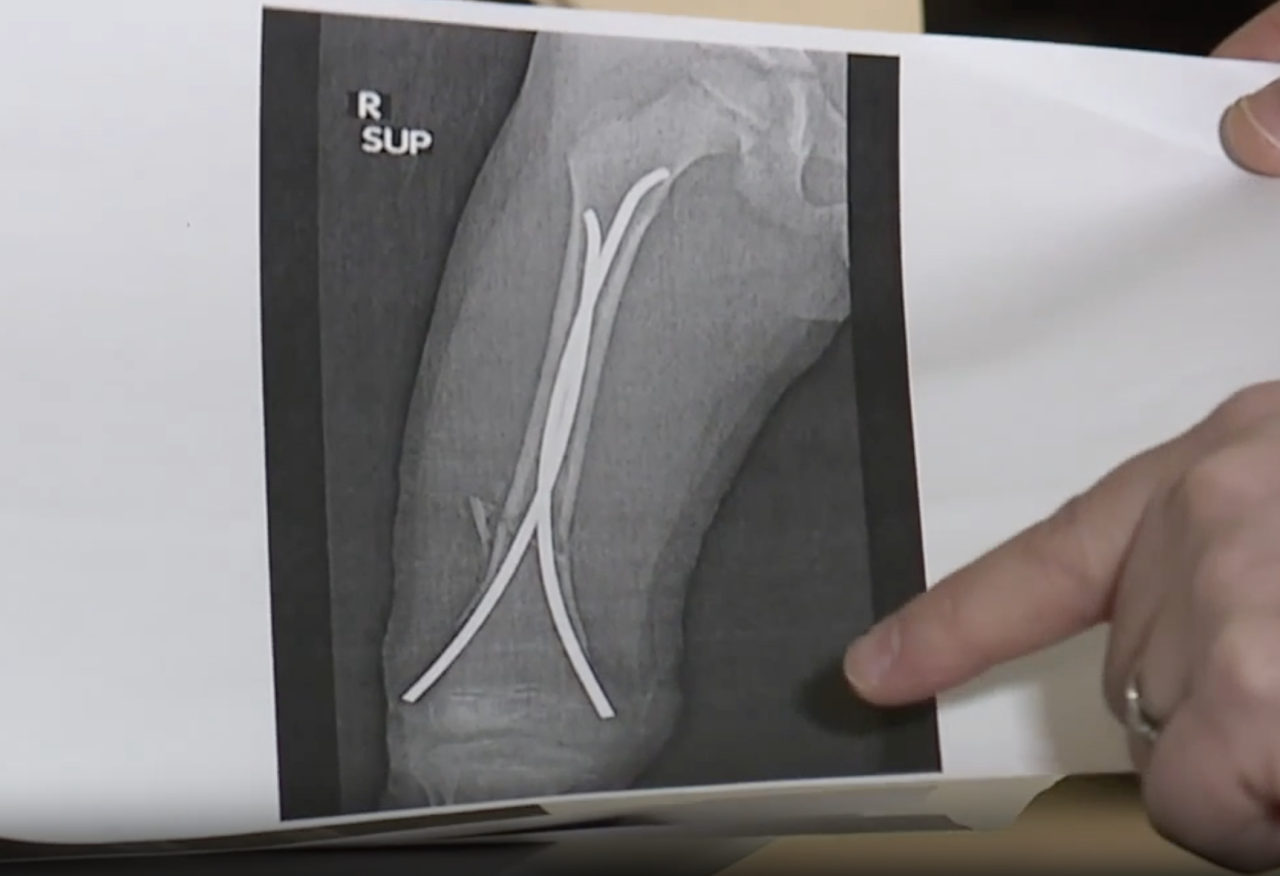

Gabriel says it happened on a slope far above his skill level — and in seconds, he went from thrill to trauma. X-rays confirmed the extent of the damage.

"This is where his leg or tibia broke in half in a spiral fashion, so it twisted. And it was significantly displaced, and it required surgery," Dr. Ahmed Bazzi, a pediatric orthopedic surgeon with Michigan Orthopaedic Surgeons, said.

With a steel rod stabilizing the bone, Gabriel was back on his feet within weeks — a recovery Bazzi calls remarkable.